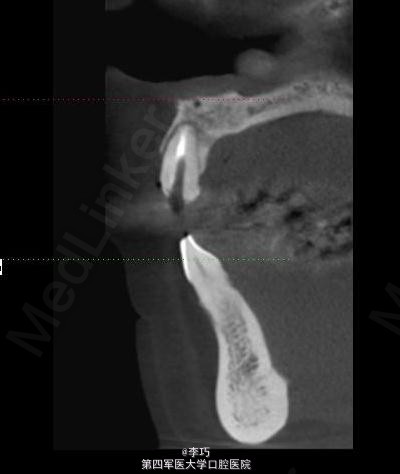

行曲面断层片和CBCT模拟植入